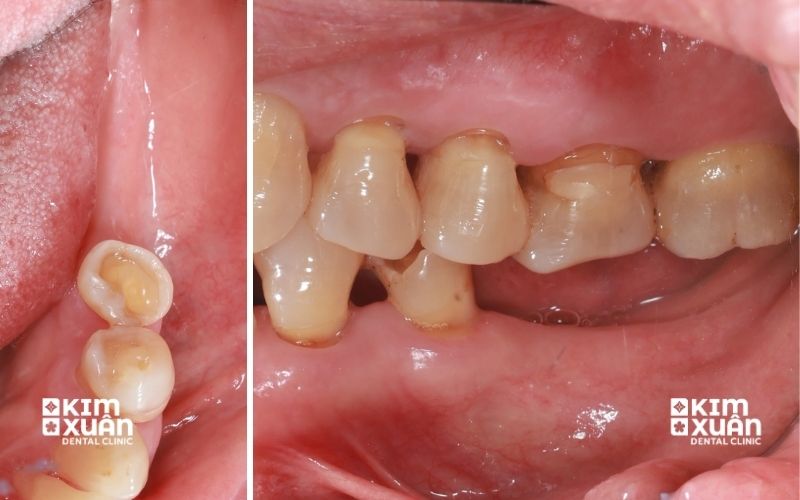

Mất răng lâu năm vẫn trồng Implant được. Có ngay cả khi răng đã mất trong thời gian dài và xảy ra tiêu xương hàm, trồng răng Implant cho người mất răng lâu năm vẫn là giải pháp phục hồi hiệu quả cả về ăn nhai và thẩm mỹ. Tuy nhiên, do xương hàm có thể bị tiêu nhiều, bác sĩ sẽ cần thăm khám lâm sàng và chụp phim CT để đánh giá mật độ xương, từ đó xây dựng phác đồ trồng Implant phù hợp.

Trong một số trường hợp, người mất răng lâu năm có thể cần thực hiện thêm ghép xương hoặc nâng xoang trước khi cấy Implant nhằm đảm bảo trụ Implant tích hợp chắc chắn với xương hàm và sử dụng bền lâu. Vì vậy, mất răng càng lâu càng nên trồng Implant sớm để hạn chế tiêu xương hàm nặng hơn, rút ngắn thời gian điều trị và đạt hiệu quả ăn nhai - thẩm mỹ tối ưu.

Mất răng lâu năm hoàn toàn có thể trồng lại được bằng phương pháp cấy ghép Implant. Đây là kỹ thuật phục hình hiện đại, trong đó bác sĩ đặt một trụ Implant vào xương hàm để thay thế chân răng đã mất, sau đó phục hình mão răng sứ bên trên.

Răng Implant sau khi hoàn thiện có hình dáng, màu sắc và chức năng ăn nhai gần giống răng thật, đồng thời giúp khôi phục thẩm mỹ khuôn mặt một cách toàn diện. Trong trường hợp mất răng đã lâu khiến xương hàm bị tiêu, bác sĩ vẫn có thể chỉ định ghép xương, nâng xoang hoặc ghép mô nướu trước khi cấy Implant để đảm bảo điều kiện phục hồi răng an toàn và bền vững.